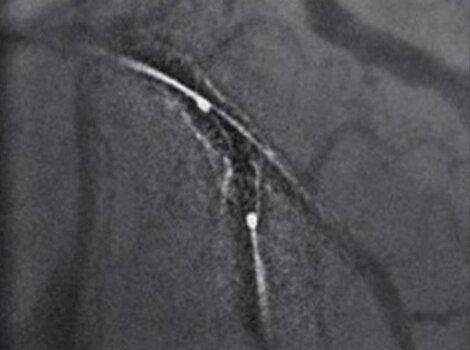

Intervention(介入)

对于送往导管室进行血运重建的患者,我们会尝试快速进入罪犯血管并完成进一步的冠状动脉评估。快速干预可以帮助减少从首次医疗接触开始的再灌注时间。

Innova IGS 5 或 Discovery IGS 7

业界对探测量子效率(DQE)的最高评级之一,可有助于减少使用造影剂和剂量。12 了解更多信息

成功的狭窄新病变 PCI 包括对罪犯病变的规划、指导和评估,以及对冠状动脉其余部分的评估。

Innova IGS 55

业界对探测量子效率(DQE)的最高评级之一,可有助于减少使用造影剂和剂量。